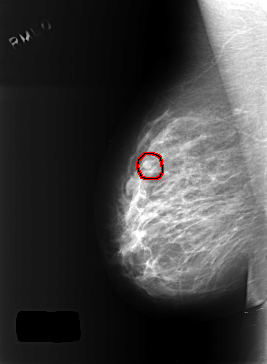

C_0402_1.RIGHT_MLO

RIGHT_MLO LINES 5448 PIXELS_PER_LINE 4000 BITS_PER_PIXEL 12 RESOLUTION 50 OVERLAY

FILE: C_0402_1.RIGHT_MLO.OVERLAY

TOTAL_ABNORMALITIES 1

ABNORMALITY 1

LESION_TYPE MASS SHAPE OVAL MARGINS CIRCUMSCRIBED

ASSESSMENT 3

SUBTLETY 4

PATHOLOGY BENIGN

TOTAL_OUTLINES 1

BOUNDARY